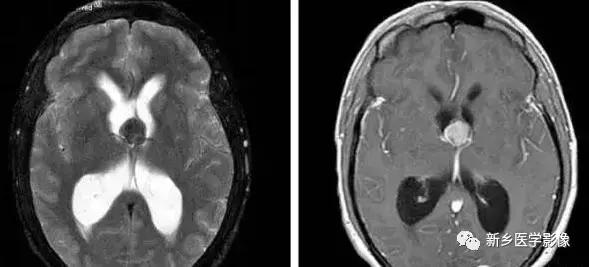

1.导水管狭窄:

中脑导水管是脑室系统最狭窄的通道,也是脑脊液循环受阻最常见的部位。

导水管狭窄的病因比较复杂、主要包括:①先天发育性狭窄②导水管周围胶样变③导水管粘连等。先天发育性狭窄可呈线样狭窄、分叉样狭窄或横膈膜形成。导水管周围胶样变多为炎症所致,主要见于宫内先天感染后,尤其是弓形体感染。

导水管粘连主要见一于颅内感染和出血后,可于胚胎期发生,也可见于出生后任何年龄。导水管粘连所致狭窄多位于导水管远端。狭窄段长度通常为2一5mm,狭窄近端异水管可呈喇叭口样扩张。

导水管狭窄时,三脑室扩大常很显著,三脑室前部视隐窝和漏斗隐窝扩张或消失,三脑室后部松果体隐窝和松果体上隐窝明显后突,向小脑上池疝入。严重者可压迫小脑。